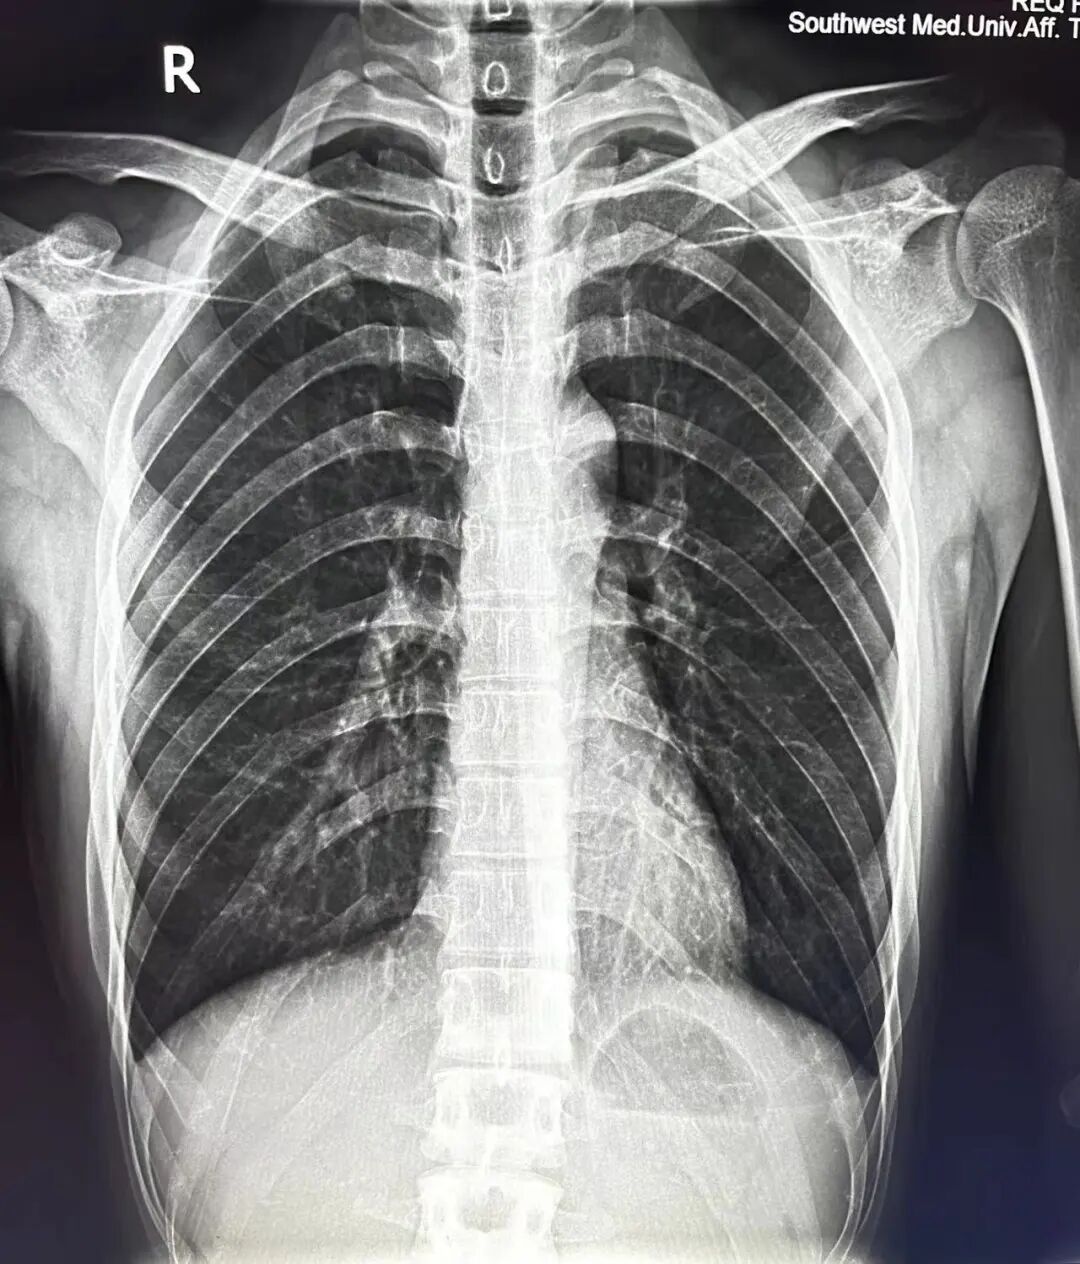

案例2、30岁患者被撞后到院检查,平片显示未见异常,CT扫描显示右侧第六肋骨不全性骨折。